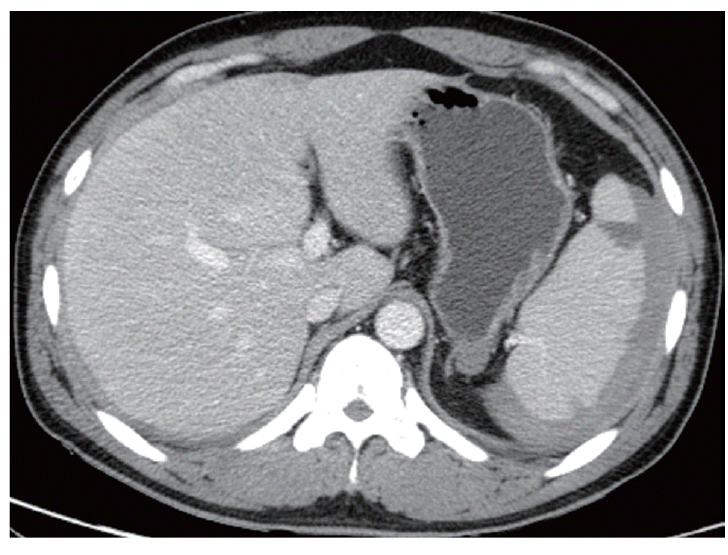

Given the characteristic intermittent fever, a peripheral blood smear and rapid blood assay for malaria were conducted. Based on the results, the patient was diagnosed with P. vivax (Fig. 1). A prompt examination with an abdominal CT revealed that the patient suffered from hemoperitoneum (36 HU on portal phase). The spleen was enlarged and surrounded by a high attenuated fluid collection (61 HU on portal phase; Fig. 2). The surface of the spleen was scalloped due to the fluid accumulation. Higher attenuation of the perisplenic fluid compared to the other site of hemoperitoneum and splenomegaly led to a diagnosis of spontaneous splenic rupture resulting in a subcapsular hematoma.